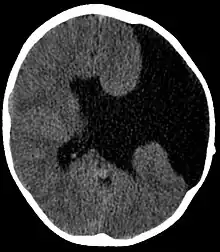

| Axial CT scan showing schizencephaly in a 6-year-old child | |

Schizencephaly (from Greek skhizein 'to split', and enkephalos 'brain')[1][2] is a rare birth defect characterized by abnormal clefts lined with grey matter that form the ependyma of the cerebral ventricles to the pia mater. These clefts can occur bilaterally or unilaterally. Common clinical features of this malformation include epilepsy, motor deficits, and psychomotor retardation.[3]

Schizencephaly can be distinguished from porencephaly by the fact that in schizencephaly, the fluid-filled component is entirely lined by heterotopic grey matter, while a porencephalic cyst is lined mostly by white matter. Individuals with clefts in both hemispheres, or bilateral clefts, are often developmentally delayed and have delayed speech and language skills and corticospinal dysfunction. Individuals with smaller, unilateral clefts (clefts in one hemisphere) may be weak or paralyzed on one side of the body and may have average or near-average intelligence. Patients with schizencephaly may also have varying degrees of microcephaly, Cognitive impairment, hemiparesis (weakness or paralysis affecting one side of the body), or quadriparesis (weakness or paralysis affecting all four extremities), and may have reduced muscle tone (hypotonia). Most patients have seizures, and some may have hydrocephalus.[4]